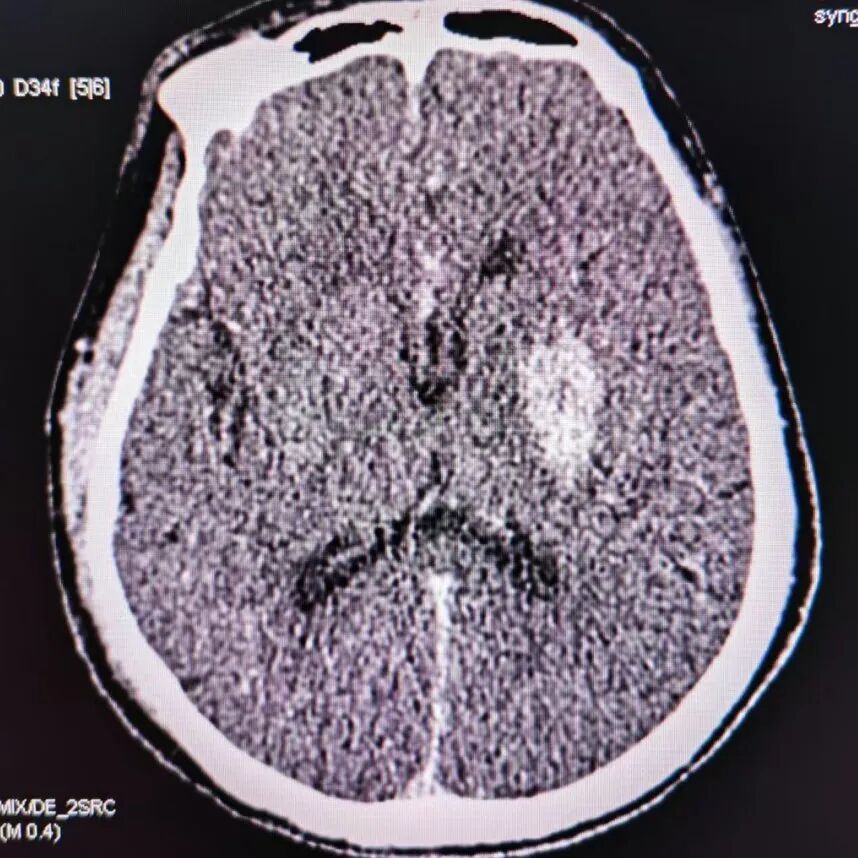

术后CT提示基底节区高密度灶。

动脉长鞘怎么置入有励可说|Locaste 088励楷长鞘及Tarvos微导丝在左侧大脑中动脉闭塞取栓术中的应用_https://www.jmylbn.com_新闻资讯_第22张

动脉长鞘怎么置入有励可说|Locaste 088励楷长鞘及Tarvos微导丝在左侧大脑中动脉闭塞取栓术中的应用_https://www.jmylbn.com_新闻资讯_第23张

去碘后考虑造影剂外渗。

动脉长鞘怎么置入有励可说|Locaste 088励楷长鞘及Tarvos微导丝在左侧大脑中动脉闭塞取栓术中的应用_https://www.jmylbn.com_新闻资讯_第24张

动脉长鞘怎么置入有励可说|Locaste 088励楷长鞘及Tarvos微导丝在左侧大脑中动脉闭塞取栓术中的应用_https://www.jmylbn.com_新闻资讯_第25张